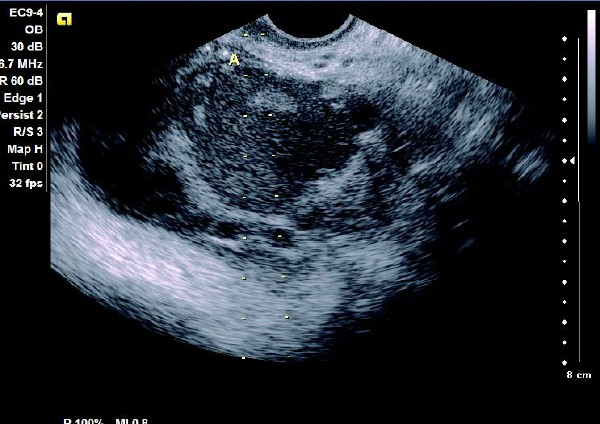

患者,女,35岁。每次月经量少,痛经,近来行经期延长、疼痛加重来院诊治。超声报告显示子宫前倾位,子宫体大小为:5.9cm×5.1cm×4.8cm,形态规则,边界清晰,宫避回声匀称,宫腔线居中,内膜厚度0.6cm,宫内未见异常回声。右侧卵巢内可见大小约5.2 cm×4.9cm的无回声区暗区,壁厚,内壁欠光滑,内见密集细光点,边界清晰。CDFI探测囊壁及囊腔内无血流信号。

超声提示:右侧卵巢巧克力囊肿